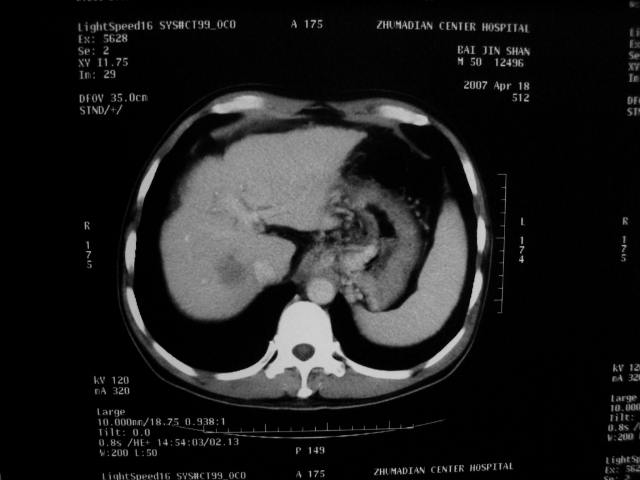

标题: CT7751:病人,50岁,肝硬化多年,行CT三期扫描 [打印本页]

标题: CT7751:病人,50岁,肝硬化多年,行CT三期扫描

动脉期病灶见轻度强化,考虑肝癌可能性大。

动脉期轻度强化 考虑 肝右叶小肝癌可能性大

肝硬化 脾大 胃底静脉曲张 肝癌 门腔间淋巴结肿大

1、肝右叶低密度灶考虑肝癌

2、肝硬化

肝硬化、脾大,静脉曲张,肝右叶低密度灶,增强无明显强化,还是考虑肝癌可能性大,建议结合afp检查。

考虑肝硬化,脾大,静脉曲张,肝右叶低密度灶,右肝癌可能性大。

肝癌分为肝细胞性和胆管细胞性,从强化表现来看,确切地说应是胆管细胞癌.